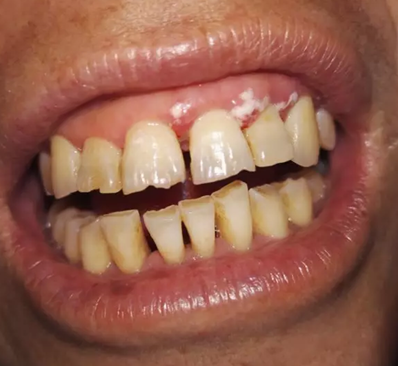

該患者本身就有慢性牙周炎,加上高血壓的基礎疾病,長期服用硝苯地平,這個是導致藥物性牙齦增生常見藥物之一,針對這樣的患者在牙周基礎治療時必要的,但在基礎治療的同時,一定要建議患者更改降壓藥物,同時必要時手術切除增生牙齦,可以達到很好的效果,見圖片(圖中白色為雙氧水沖洗后效果)。